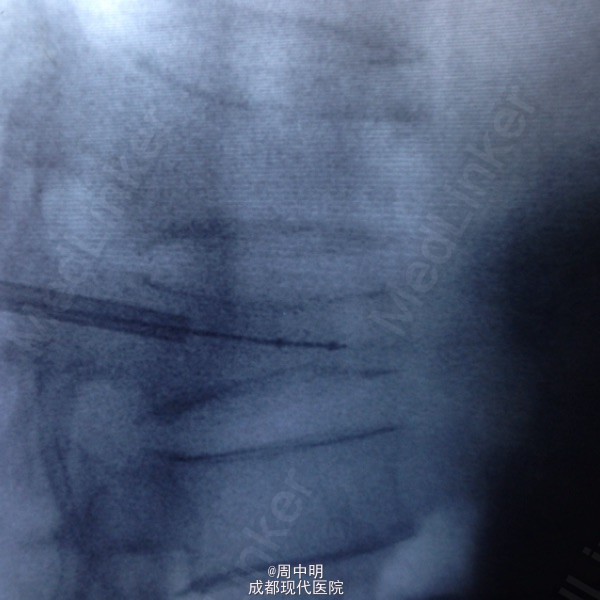

87岁,男性,T11压缩骨折

胸椎11压缩骨折